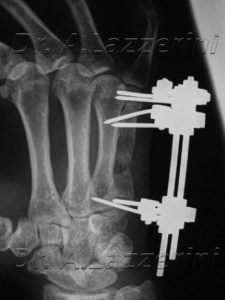

Pseudoartrosi del 5° metacarpale, con significativo accorciamento.

Trattata con fissazione esterna LAKI sec. la metodica di Ilizarov:

Osteotomia prossimale e compattazione del frammento intermedio alla pseudoartrosi.

Allungamento.

Consolidazione del rigenerato.